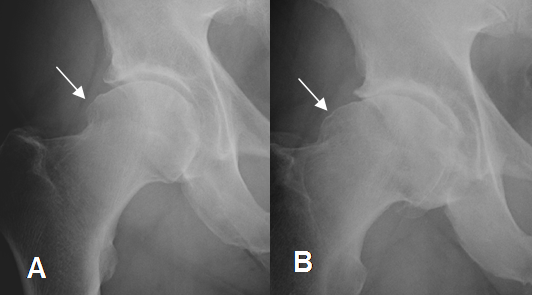

Fig 101. Pinzamiento tipo cam.

A y B: Rx AP de cadera. Prominencia en la parte externa de las cabezas femorales, en diferente grado, produciendo el signo de la empuñadura de pistola.